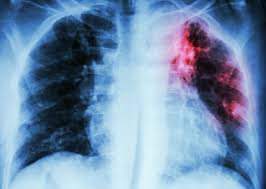

Dr. Bagana revealed that data from 2025 showed 127,410 total presumptive TB cases in the state, with 126,228 of them tested. Of these, 14,908 were confirmed as tuberculosis cases, and 8,629 have been fully cured using advanced diagnostic tools, including the Genexpert Machine, Trunat Machine, T LAMP, and PDX Machine.

Tuberculosis remains a major public health concern in Nigeria, with high rates of infection and challenges in treatment adherence. Niger State’s efforts to identify and treat more than 8,600 confirmed cases represent a significant achievement, but experts caution that success depends on sustained funding, public awareness, and strong healthcare infrastructure.